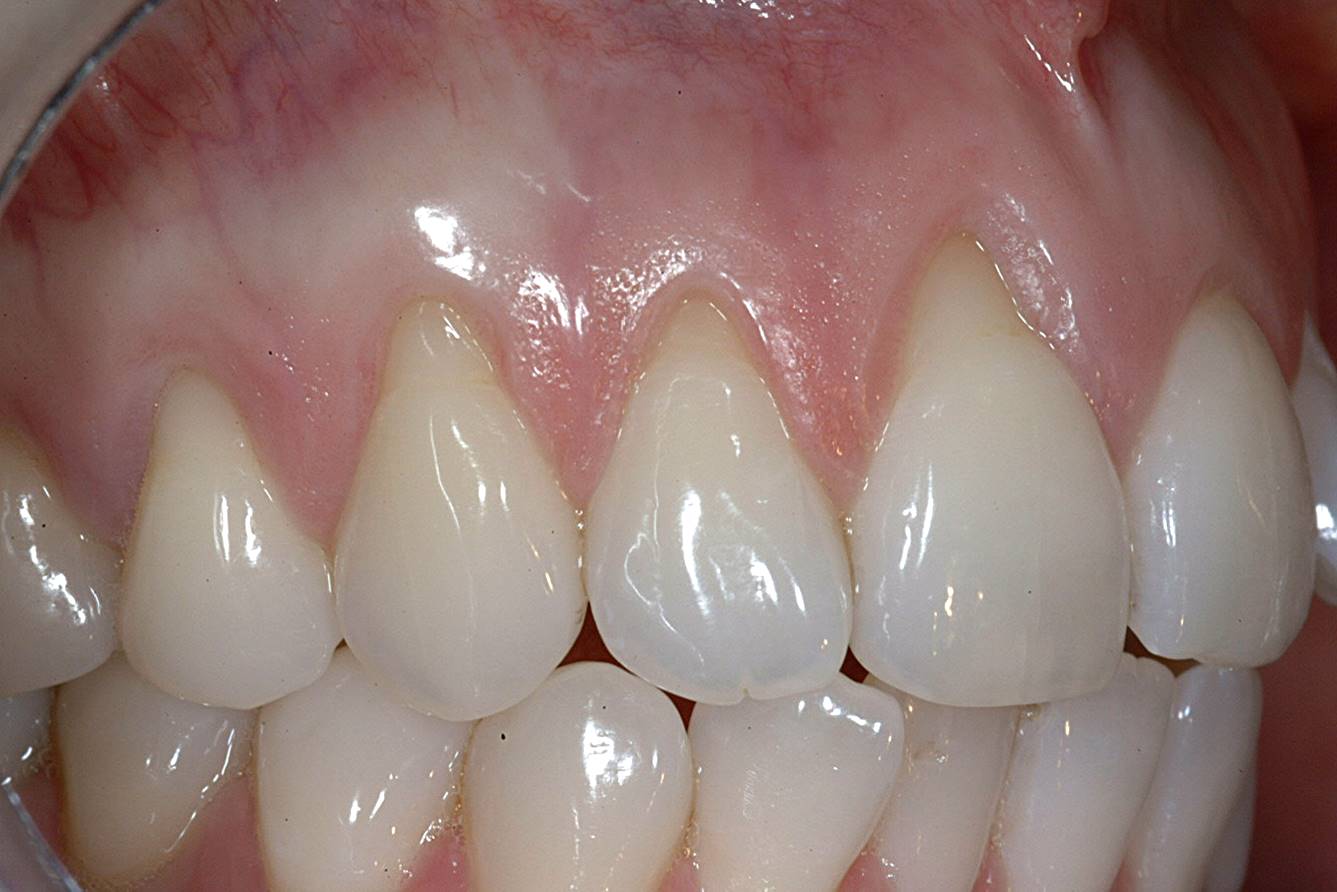

A patient presented with moderate recession requiring root coverage and increased thickness of the alveolar housing (Figure 9). A series of parallel incisions was completed using instruments made specifically for microsurgery; these incisions were performed utilizing high magnification (ie, 5.5 magnification via loupes). The distance between the incisions was roughly the amount of root coverage necessary on the adjacent teeth (Figure 10).25

The isthmus of tissue between the parallel incisions was removed. A split-thickness flap was elevated leaving connective tissue on the bone and providing access for root preparation.

To ensure a smooth root surface, rotary instruments with finishing burs and curettes are used. A glycine air-polishing unit (eg, Air-Flow Master, Hu-Friedy, hu-friedy.com) was used to impart the final smoothing of the roots and remove the smear layer and biofilm.

The CTG was then harvested from the palate as previously described and placed over the roots (Figure 11). The primary flap was advanced to cover the graft; a dual blood supply was assured from the underlying tissue and the overlying flap. Atraumatic suturing was performed using fine sutures (eg, Resorba® 6-0/7-0 Resolon™, Osteogenics Biomedical, osteogenics.com) to approximate the flap margins.

After 1 week, rapid healing and good closure were observed. After 2 years, complete root coverage was visible, a thicker alveolar housing was achieved, and the gingiva was more resistant to future breakdown (Figure 12).